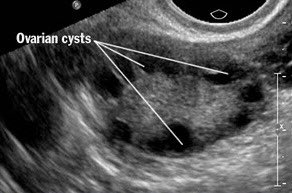

📍Polycystic Ovary Syndrome (String of pearls)